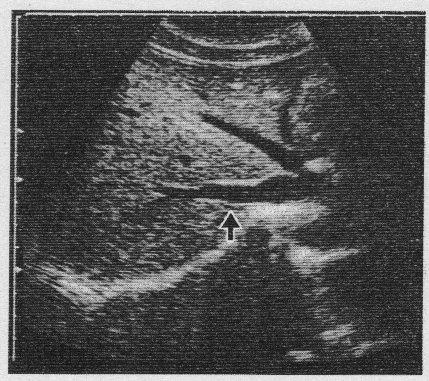

問題 70  図の超音波画像で正しいのはどれか。

1. 右肋間走査である。

2. Mモード画像である。

3. 図の矢印は門脈である。

4. 肝臓の右葉が描出されている。

5. ミラー現象によるアーチファクトが見られる。